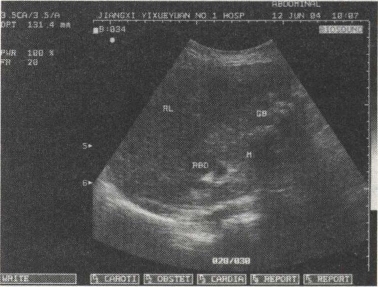

42.男,48岁,血吸虫疫区接触史,肝区胀痛,脾肿大。结合超声声像图,诊断为()